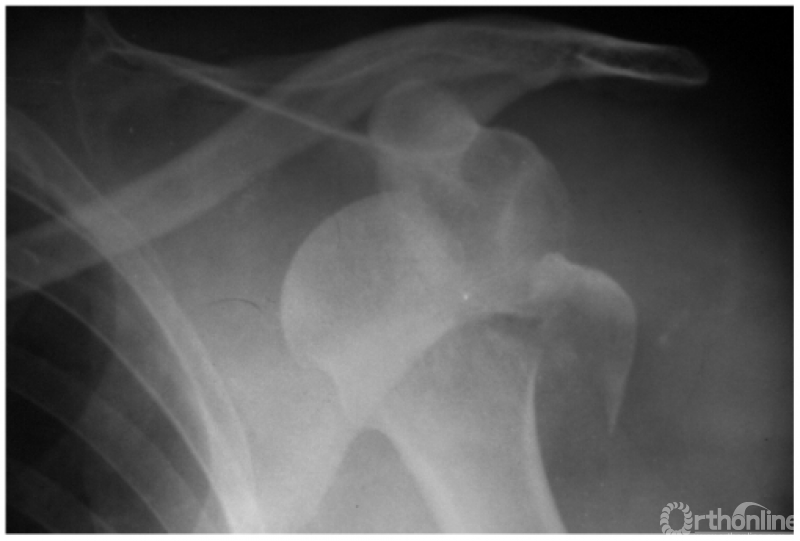

例3:肩关节喙突内下方脱位并大结节及肩峰端骨折(如下图)。

例4:肩关节盂下脱位并解剖颈骨折:致肱骨头仍滞留在盂下,而远折端回至关节盂部,形成假关节(如下图)。

例5:肩关节喙突下脱位并外科颈劈裂骨折及同侧锁骨中断骨折(如下图)。